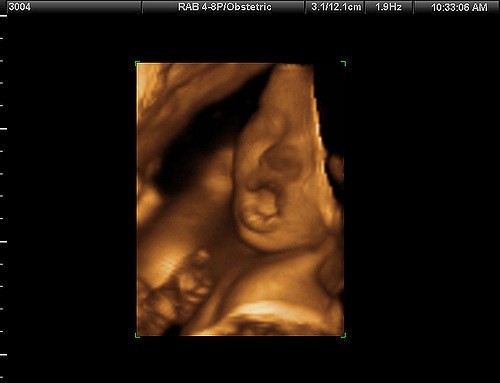

Kobiety otrzymały radę, aby takie zagadnienia jak adopcja czy badanie USG "wygooglały sobie w internecie", ponieważ Planned Parenthood "nie prowadzi takich usług". Jednak w kwestii badań jest to sprzeczne z tym, co jest zaprezentowane na oficjalnej stronie Planned Parenthood, gdzie w zakładce "Usługi dla kobiet" znajdziemy całą listę badań, które tam się wykonuje, m.in.: USG, badanie piersi, badanie szyjki macicy, kolposkopia, leczenie menopauzy i "inne usługi z zakresu zdrowia kobiety".

Pracownice organizacji, z którymi rozmawiały podstawione kobiety, uświadomiły swoje rozmówczynie, że takie badania jak USG wykonuje się tylko w przypadku aborcji. "To jedyna usługa, którą tu wykonujemy" - powiedziała pracownica. "Nie prowadzimy żadnej opieki prenatalnej ani adopcji".